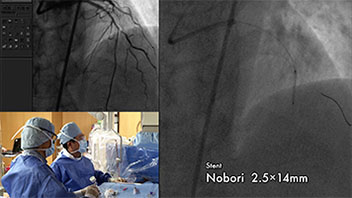

ノンフィクションにおいて重要なことは、間違った解釈をされないようにモンタージュをおこなうことです。デザインや特殊効果ばかりを意識して、本来有るべき編集の果たす役割を間違って展開させると真実を伝える事ができません。技術紹介や医療解説に嘘や間違いは許されません。写楽ではこの事に充分注意しながら、理解をより深める技法としてモーションやエフェクトを効果的に使用して編集を行っています。

写楽では、より専門性の高い工業系や医療系ビデオ編集において、完成した映像を見て頂く専門家の方へ正確に訴求ポイントが伝えられるように工夫する事を心がけています。それを可能としているのが、工学、医学の知識を持った技術スタッフです。

実写だけでは正確に伝えられない内容や表現できない場合は、コンピュータグラフィックアニメーションで補完します。その場合も制作する側が正確に原理・原則を理解していないと、微妙なニュアンスを伝える為の表現ができません。機器の構造・特性を理解し、人体の病理学的性質を考慮しながらアニメーションをシミュレートして完成させます。